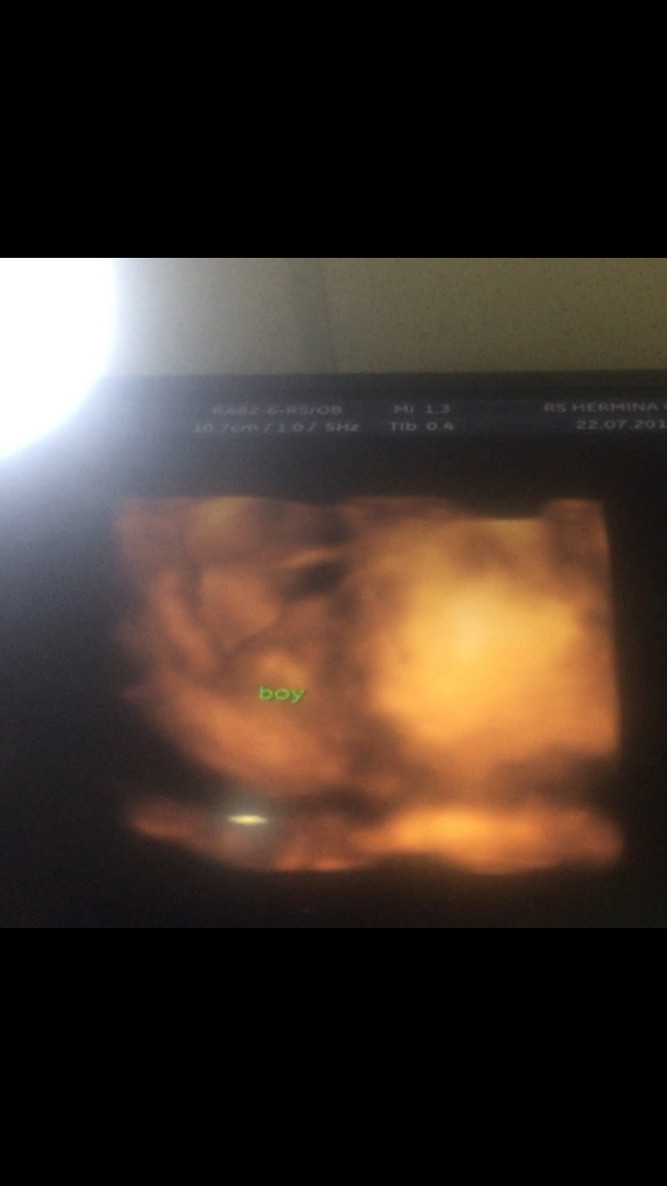

Ini waktu 32weeks, boy👶🏻